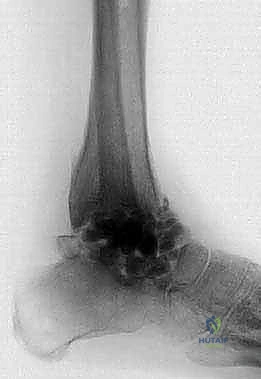

1. الأشعة السينية (X-rays): لتقييم مدى تدمير المفصل، وجود تشوهات، وفقدان العظم. يتم أخذ صور في وضعيات مختلفة (أمامية، جانبية، وأثناء الوقوف إن أمكن).

2. الأشعة المقطعية (CT Scan): ضرورية جداً للتخطيط الجراحي. توفر صوراً ثلاثية الأبعاد تُظهر بدقة كمية العظم المتبقي، جودة العظم، ومواقع التكيسات أو النخر العظمي.